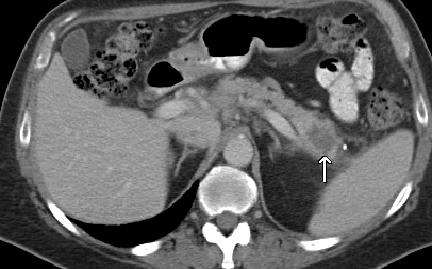

Collision Tumors: Pancreatic Adenocarcinoma and Mantle Cell Lymphoma

Context Collision tumors are very rare entities composed of two or more distinct tumor components, each separated by normal tissue. Perhaps due to technical advances in the last decade, the incidence of collision tumors has been on the rise. To the best of our knowledge, collision tumors featuring mantle cell lymphoma and pancreatic adenocarcinoma have not been previously described in the scientific literature. Case report For the first time, we describe herein the clinical course of a collision tumor between pancreatic adenocarcinoma and mantle cell lymphoma. Discussion We hypothesize several aspects in the pathogenesis of a such event and review the existing literature on collision tumors.

PET/CT scan showing extensive FDG-avid tumor featuring